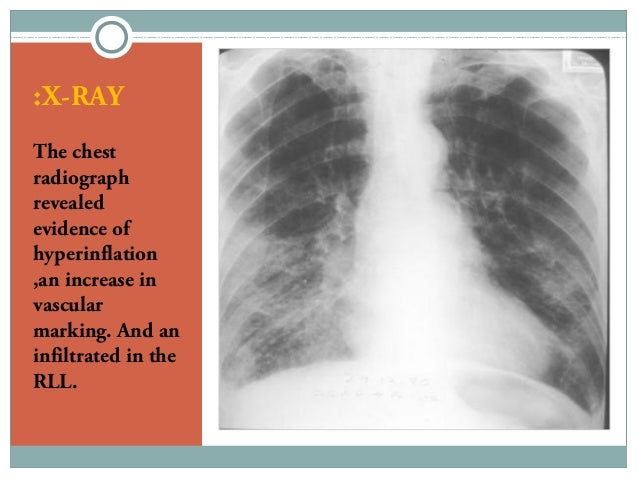

View What Is Chest X Ray Report US. Data contains two files, one for images and the other. In fact every radiologst should be an expert in chest film reading.

Chest radiographs are the most common film taken in medicine. Pneumonia, atelectasis, pneumothorax, pleural effusion. What does the equipment look like?

What we see is actually the highest point of the right diaphragm, which is anterior to the pneumonia in the right lower lobe.

Data contains two files, one for images and the other. What does the equipment look like? Data contains two files, one for images and the other. Pneumonia, atelectasis, pneumothorax, pleural effusion.